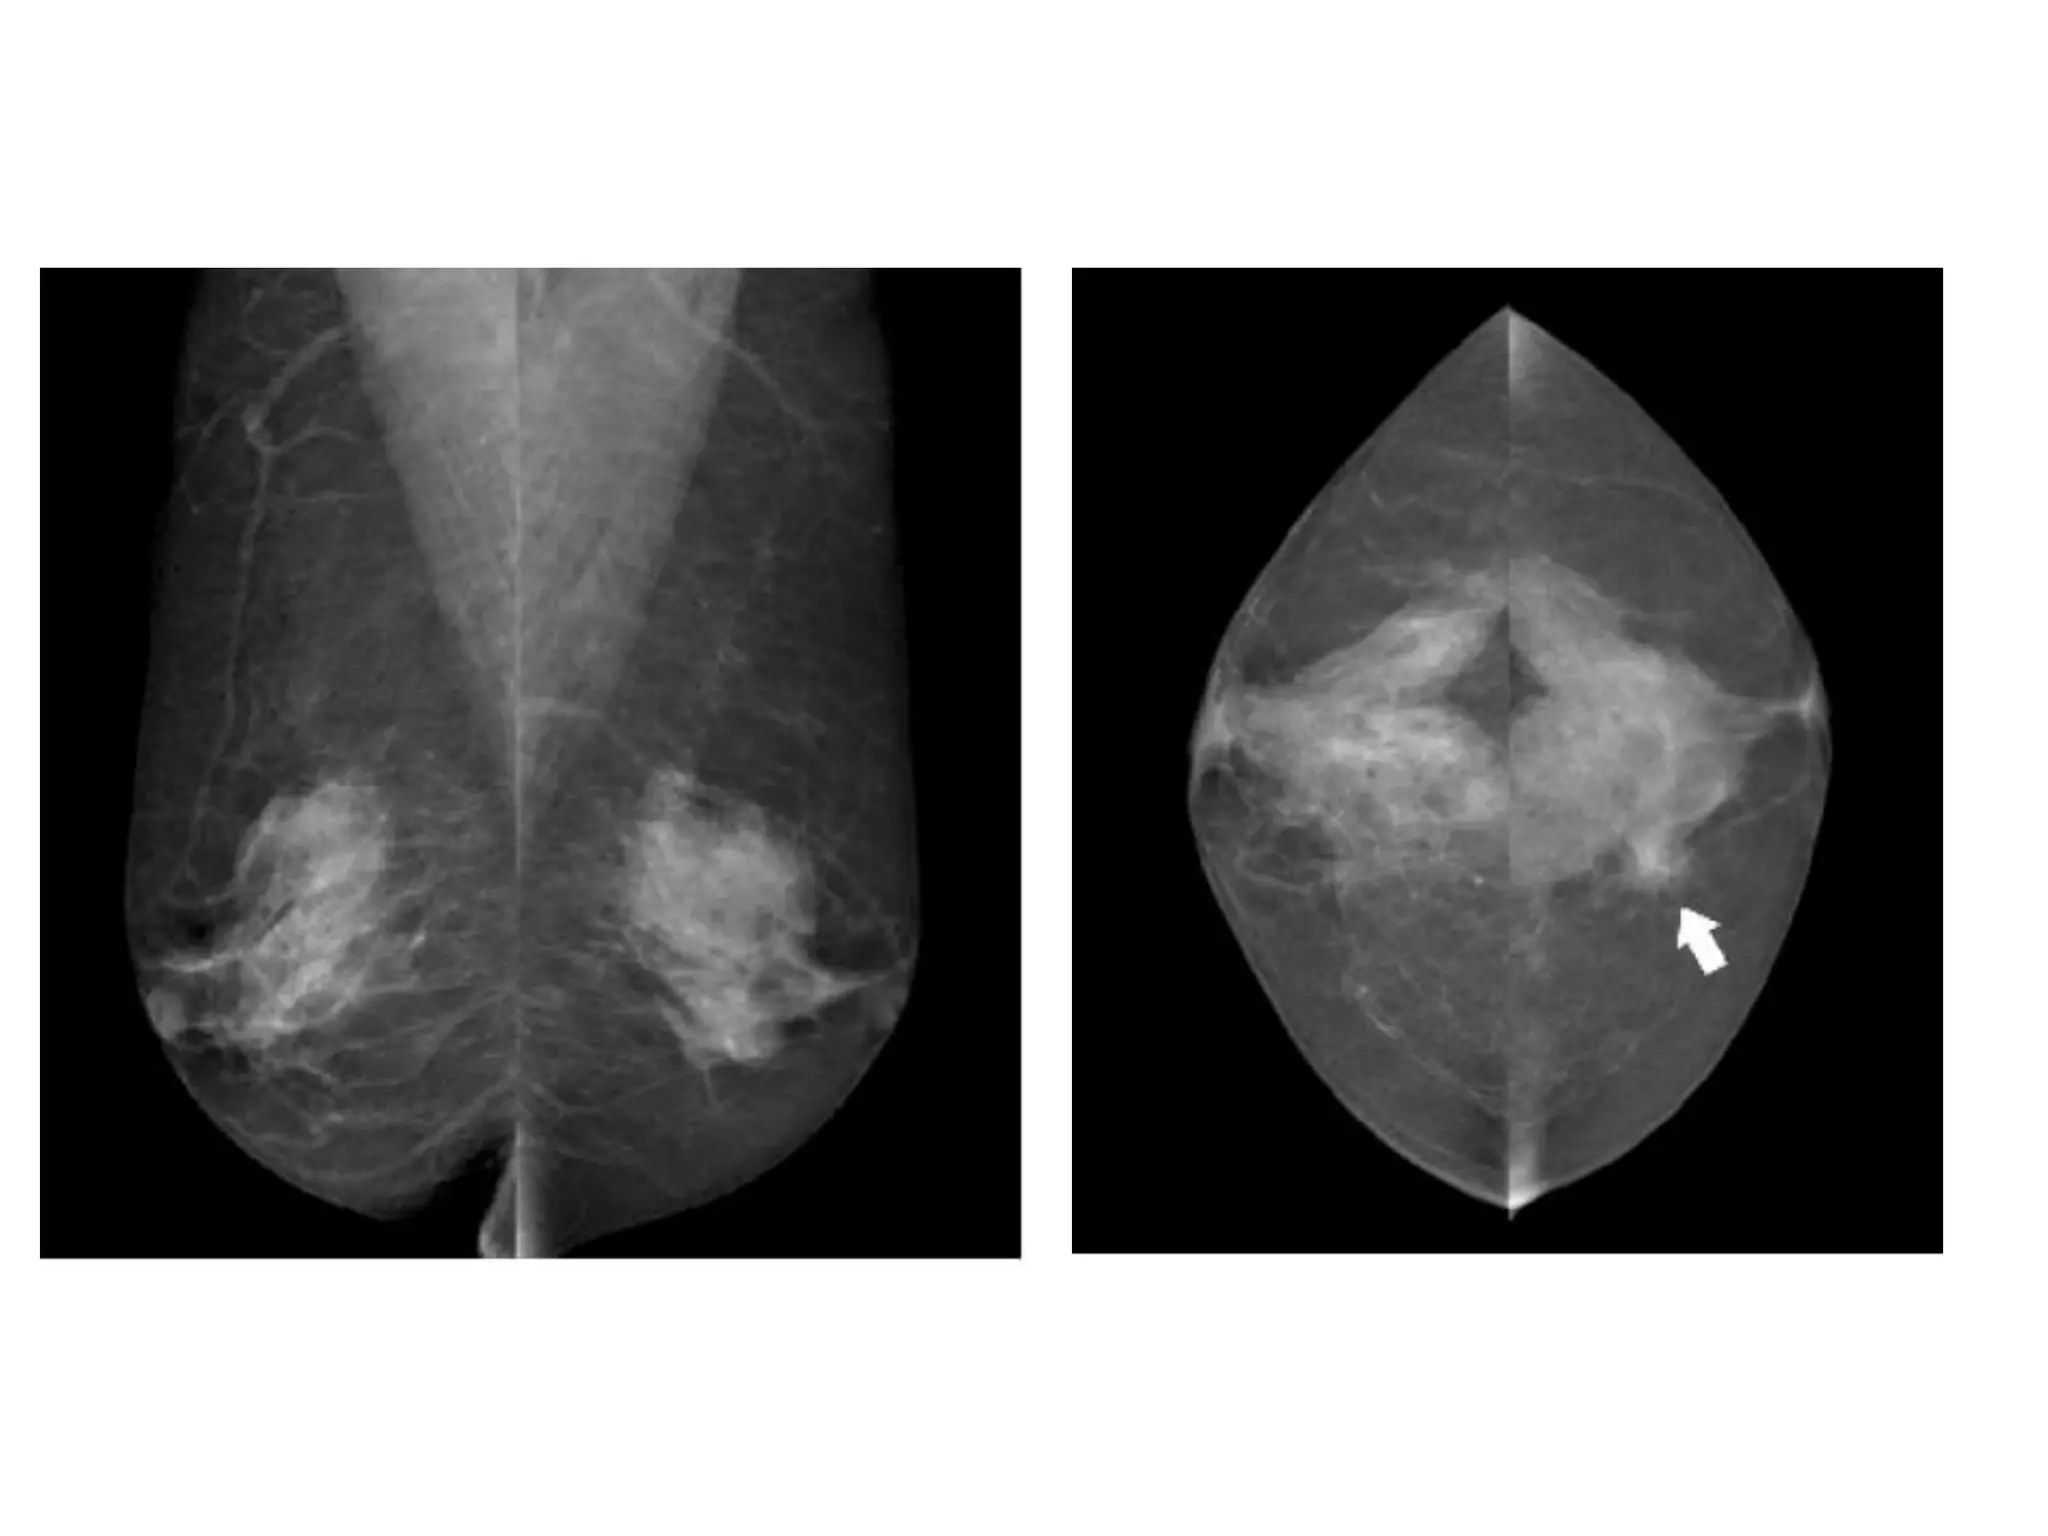

• #52 Figure 3: Global asymmetry seen in (a) schematic, (b) MLO views, and (c) CCviews. A much greater volume of breast tissue is seen over a substantial portion of theleft breast relative to the corresponding region in the right breast, but there is noassociated mass, suspicious calcifications, or architectural distortion.

• #54 Figure 4: Focal asymmetry seen in (a) schematic, (b) MLO views, and (c) CC views.A focal asymmetry with a similar shape (arrows), not fitting the criteria of a mass, isseen on two standard views.Developing AsymmetryThis is a focal asymmetry that is new, larger, or denser at current examination thanat previous examinations (Fig 5). To identify such a lesion, comparison with previousmammograms is critical. It raises a reasonable degree of suspicion and requiresadditional evaluation in the absence of a history of hormonal therapy, surgery, trauma,or infection at the site. It is an uncommon mammographic finding, reported in less than1% of examinations, but the likelihood of malignancy ranges from 13% to 27% (Fig 6)(4).5a.10